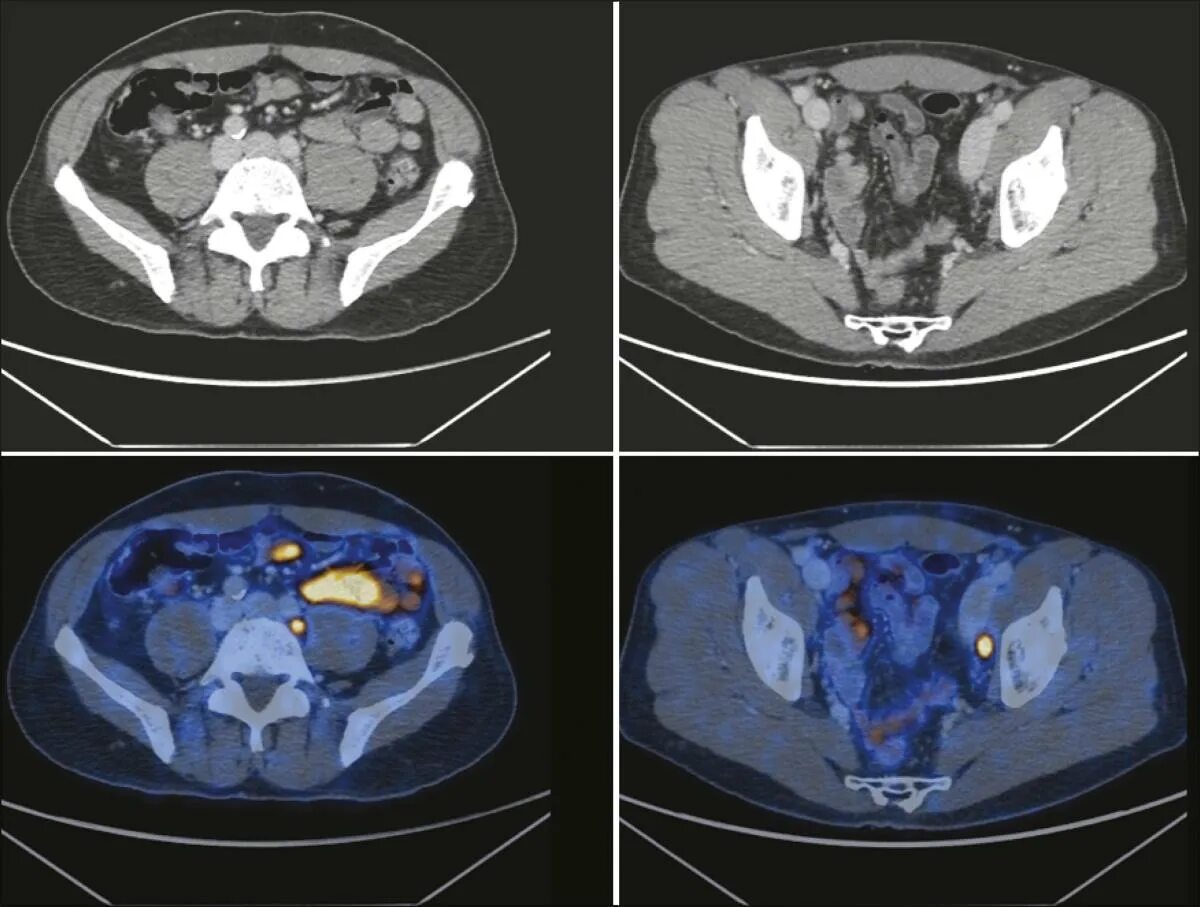

Пэт кт